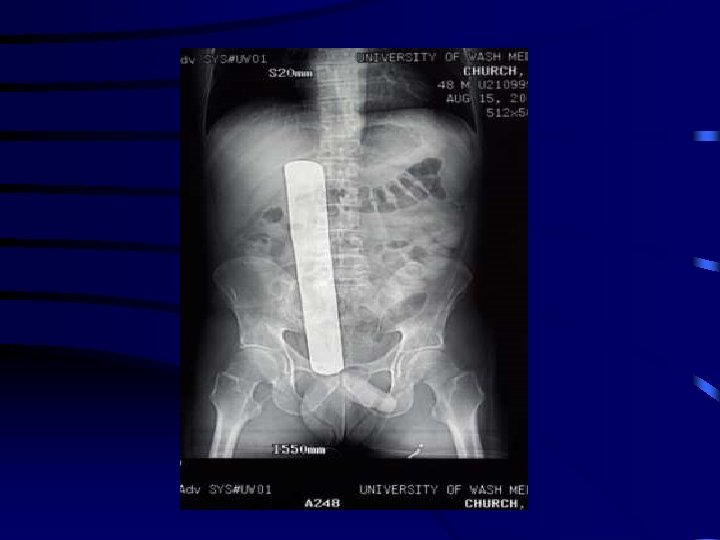

Scenario 3: Retained Sponge You are seeing a patient 3 weeks post-elective splenectomy for ITP. The splenectomy was technically challenging due to the patient’s obesity, but appeared to be uncomplicated. At this follow-up visit, the patient complains of vague, persistent LUQ pain. You send the patient for an abdominal x-ray, which shows a foreign body consistent with a retained surgical sponge in the patient’s LUQ. You remember that the sponge count was correct at the end of the procedure. However, you also remember that you packed off a small bleeding vessel near the stomach with a sponge, and now do not recall removing this sponge. When you review the postoperative records, you observe that a math error was responsible for a falsely correct sponge count. You believe a re-operation to remove the retained sponge is indicated, and expect the patient will make a full recovery.

How likely would you be to disclose this error to the patient? Response US Surgeons Canadian Surgeons I would definitely not disclose this error 0. 6% 0. 3% 0. 5% 0. 6% I would disclose this error only if asked by the patient 0. 0% 3. 0% 1. 3% I would probably disclose this error 3. 2% 2. 4% 31. 8% 22. 8% 96. 2% 97. 3% 64. 8% 75. 3% I would definitely disclose this error

What would you most likely say about what happened? Dialogue The x-ray showed an abnormality that could be serious. Another operation will be required to investigate and correct this problem. During the surgery, a sponge was inadvertently left in your abdomen. Another operation will be required to remove the sponge. We will have to do another operation because an error happened and a sponge was left in your abdomen. US Surgeons Canadian Surgeons 3% 2% 1% 1% 83% 79% 28% 21% 14% 19% 71% 78%

What would you most likely say regarding an apology? Dialogue I would not volunteer that I was sorry or apologize. I am sorry about what happened. I am so sorry that you were harmed by this error. US Surgeons Canadian Surgeons 19% 13% 3% 3% 72% 69% 54% 48% 9% 18% 43% 49%